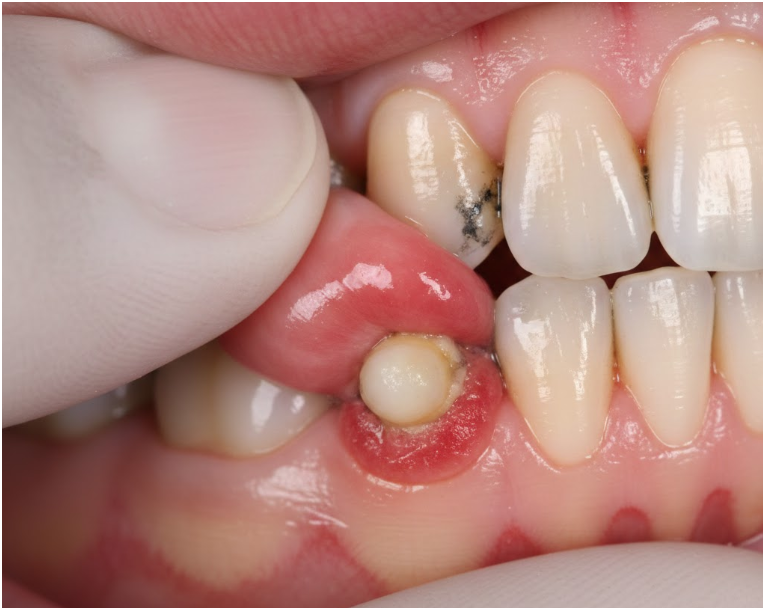

آبسه دندان تجمع چرک ناشی از عفونت باکتریایی است که در بافتهای اطراف دندان یا در انتهای ریشه ایجاد میشود. این عفونت معمولاً به دلیل پوسیدگی عمیق، ترک دندان، ضربه یا بیماری پیشرفته لثه رخ میدهد.

1) آبسه پریآپیکال

در انتهای ریشه ایجاد میشود و معمولاً ناشی از پوسیدگی عمیق درماننشده است.

2) آبسه پریودنتال

در بافتهای نگهدارنده دندان ایجاد میشود و اغلب با بیماری لثه مرتبط است.

3) آبسه لثه

سطحیتر است و معمولاً به دلیل گیر کردن جسم خارجی ایجاد میشود.

1) تخلیه آبسه

اگر چرک تجمع یافته باشد، دندانپزشک با ایجاد برش کوچک در لثه یا از طریق کانال دندان، چرک را تخلیه میکند.